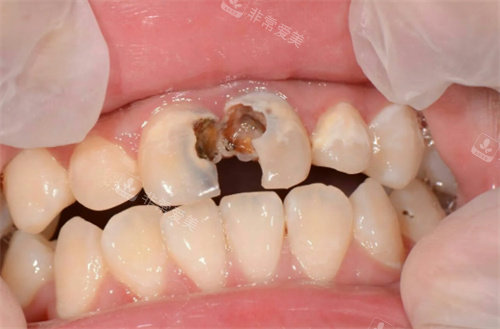

牙齿龋坏

韩四新口腔:特色技术与贴心服务并重

韩四新口腔拥有一支技术优质、经验充足的特色医疗团队。

医生们具备扎实的口腔医学知识和多年的临床经验,能够比较准诊断各种口腔问题,并提供个性化的治疗方案。

无论是常见的龋齿、牙周炎治疗,还是复杂的牙齿矫正、种植牙手术,他们都能游刃有余地应对。